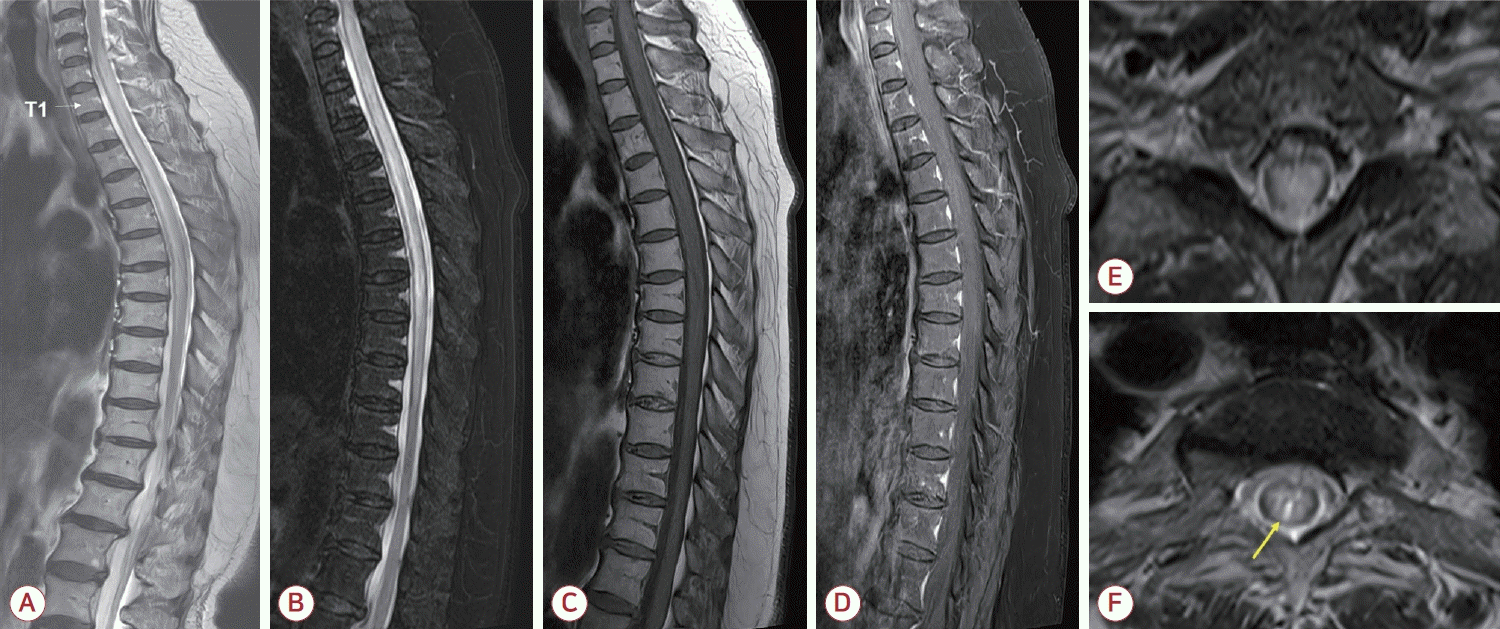

Figure.

Spine magnetic resonance imaging (MRI) findings of the case patient. (A) Sagittal T2-weighted image of the whole spine demonstrated a longitudinally extensive lesion extending from C6 to T9 (white arrow indicating the level of T1 vertebral body). (B) Fat-suppressed T2-weighted image showed mild cord swelling, and (C) corresponding T1-weighted image revealed subtle hypointensity in the same region. (D) Post-gadolinium T1-weighted image did not demonstrate abnormal enhancement. (E) Axial T2-weighted image at the C7 level and (F) at the T3 level showed extensive hyperintense lesion involving the central gray matter with a focal hyperintense area. In panel (F), a brighter spotty lesion is indicated by a yellow arrow.